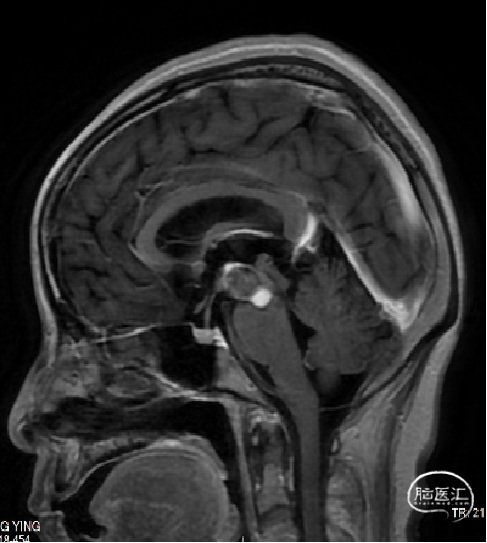

术前诊断:中脑及脑桥左份、左侧基底节区占位:海绵状血管瘤可能。

术前MRI